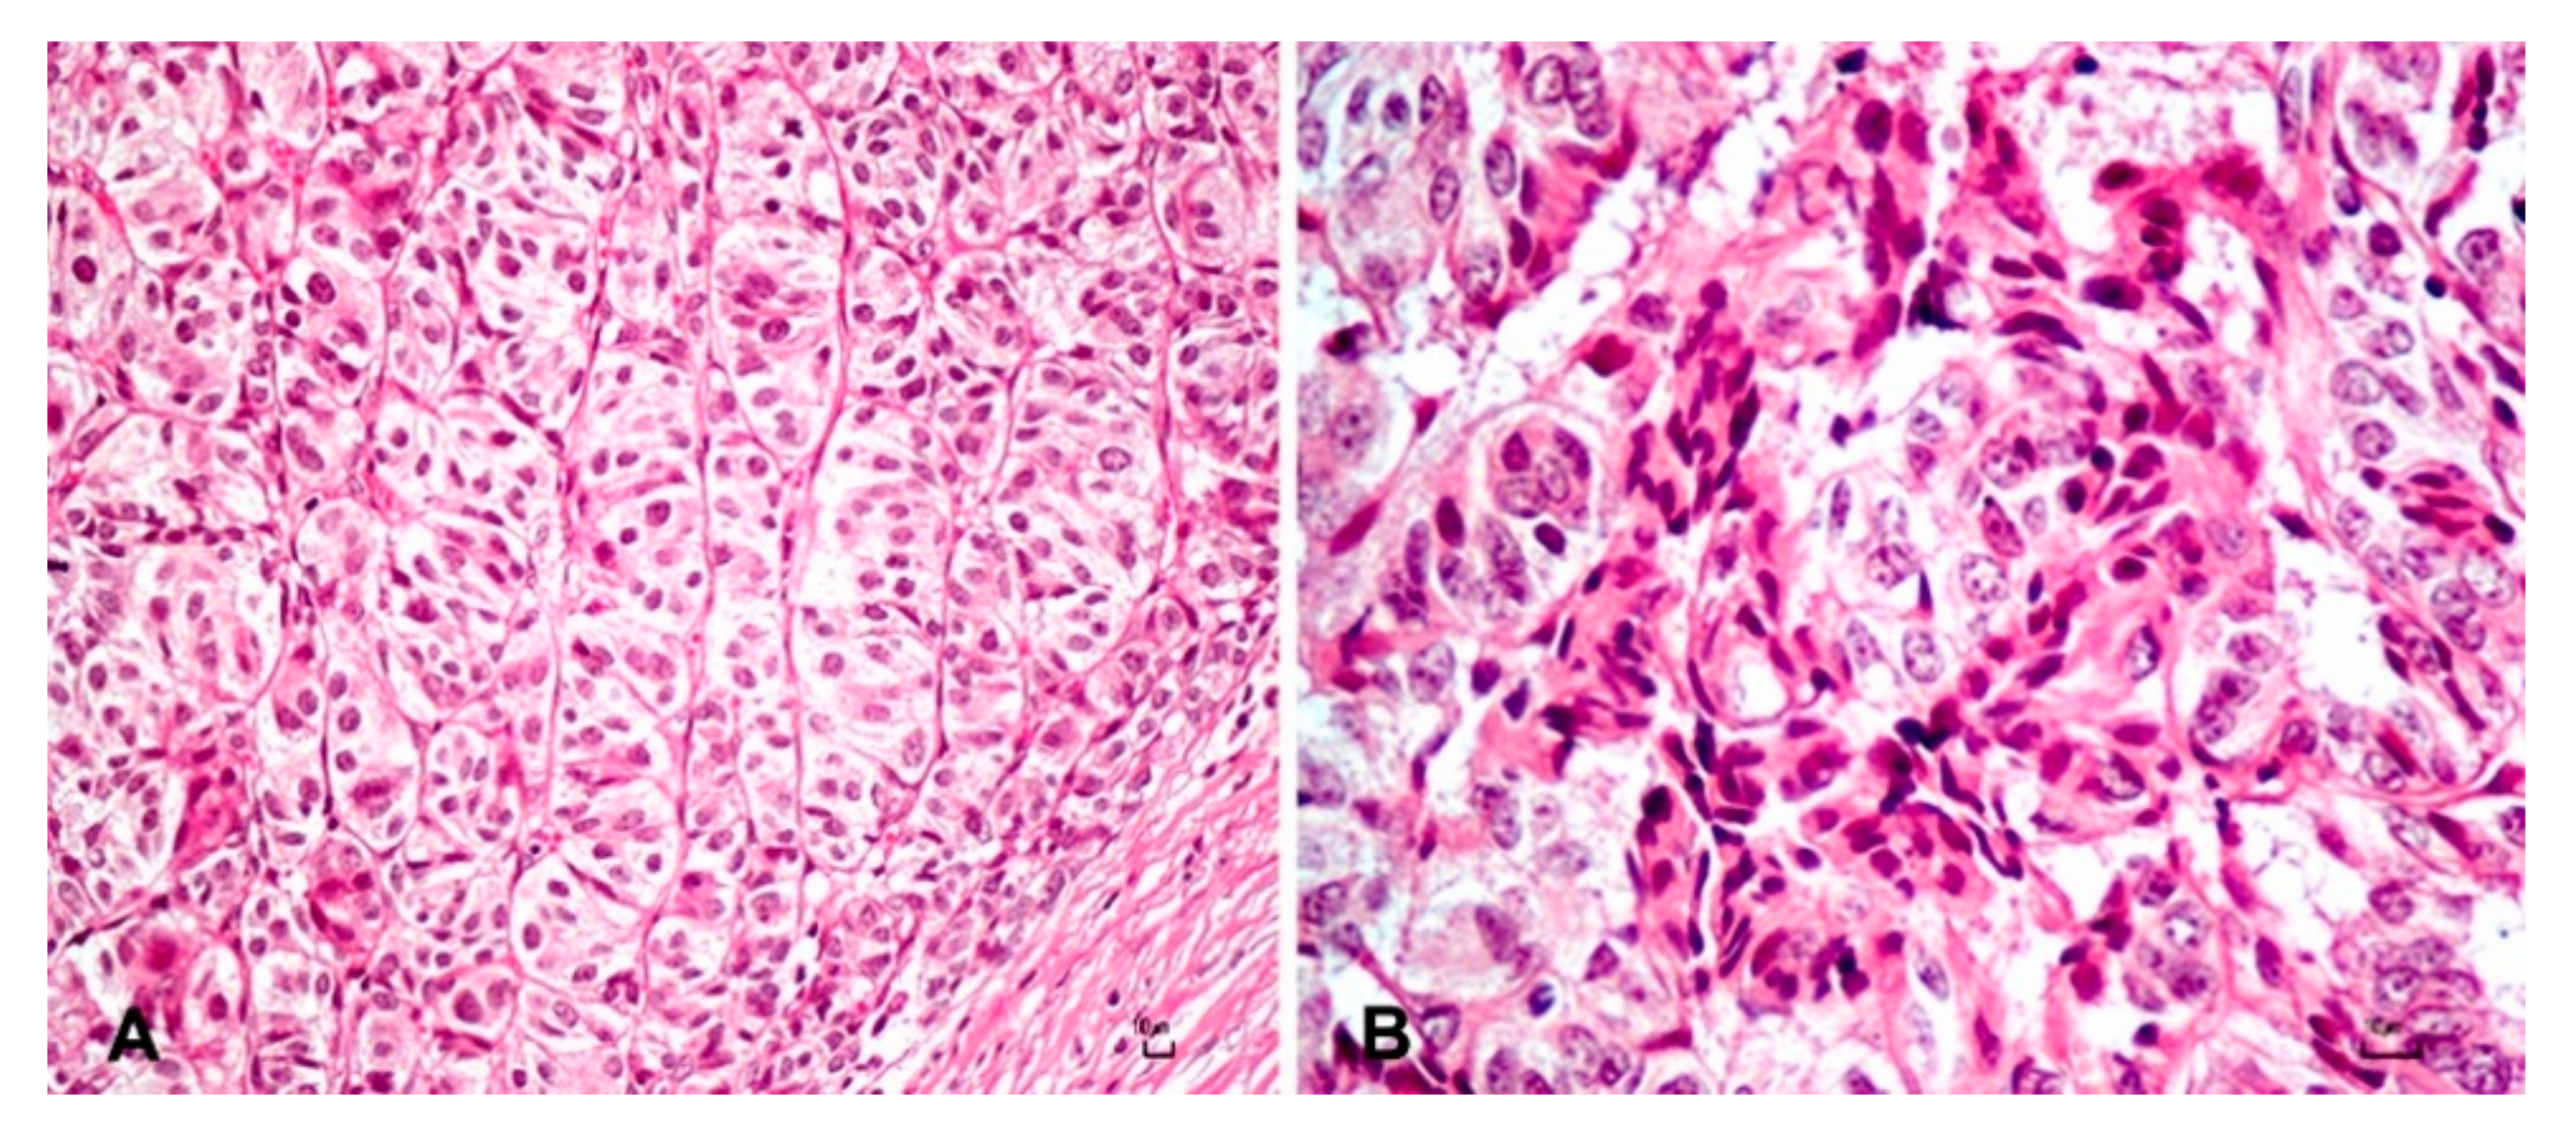

| Tumor | CK AE1/AE3 | CK 34BE12 | CK 5/6 | p63 | KI-67 | CD56 | Melan-A |

|---|---|---|---|---|---|---|---|

| Trichoblastoma | ++ | ++ | ++ | ++ | + | + | − |